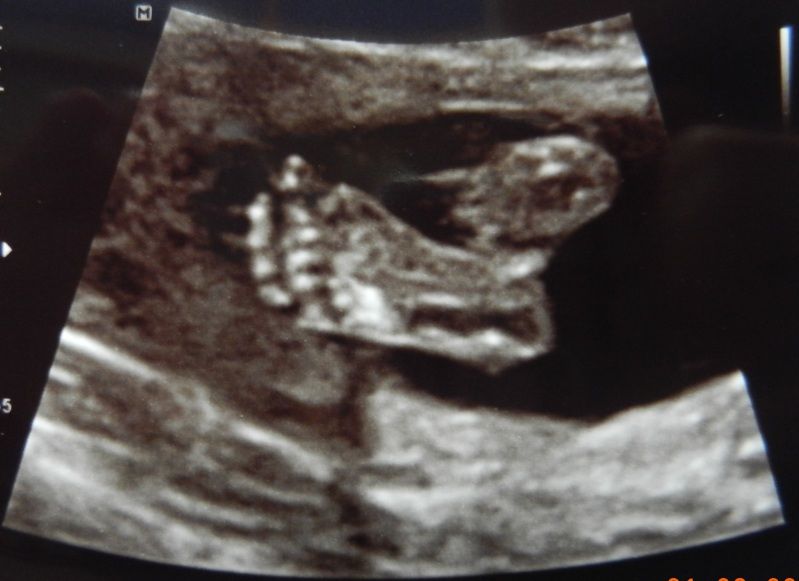

Voetje's (ML dacht tijdens de echo trouwens een champignonnetje te zien maar dat weet hij niet zeker):